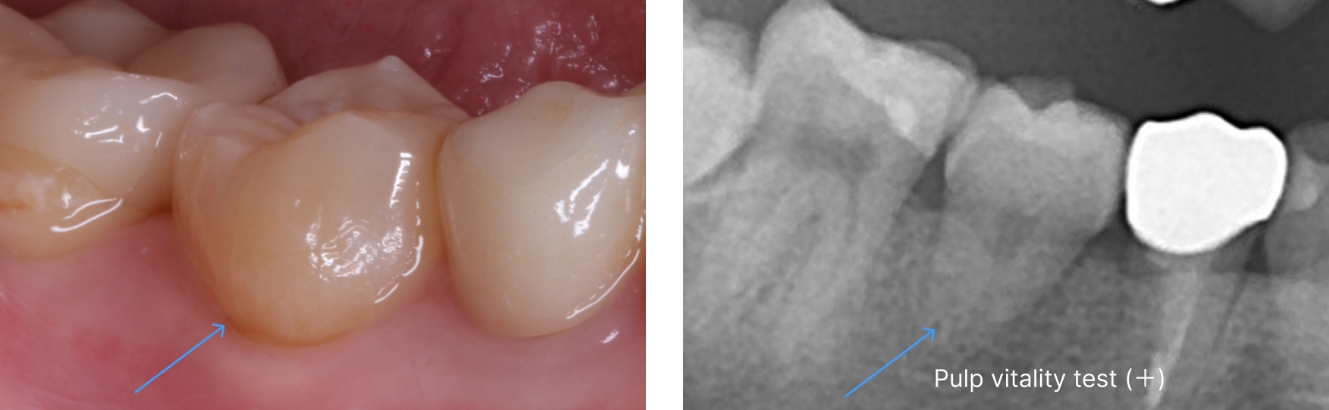

以下の写真の患者様は、移植した歯の歯根根の成長がまだ終わっていなかったため、歯を削ったり神経を取ったりすることなく、移植から11年経った現在も、そのままの状態で自分の歯として元気に機能しています。